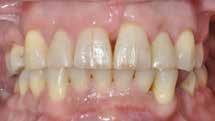

I samråd med patienten og egen tandlæge* afstemmes forventningerne, inden der bestilles refinement alignere. Nivelleringen af alle tænder i tandbuerne, smilelinje og -kurve samt den bukko-lingvale position af incisiverne foretages og efterfølges af retainers lingvalt på over- og underkæbeincisiver (Fig. 3 A-D). Hele behandlingen udføres under løbende kommunikation med patient og egen tandlæge*, der udfører den efterfølgende rekonstruktion med direkte plast (Fig. 4 A-D). Behandlingsvarigheden har været to år og to måneder, hvor ortodontien har forløbet over 21 måneder. Der har været anvendt et første sæt på 66 alignere samt yderligere to sæt med ni refinement alignere. Tandblegning og direkte plastrekonstruktion er udført af egen tandlæge* (Fig. 5 A-F).

Fig. 5. A, B. Smil og kæbeforhold før og efter. Et bredere smil med korrektion af de laterale mørke rum. C-F. Harmonisk hældning af overkæbe- og underkæbeincisiver, rekonstruktion af den tabte tandsubstans efter nivellering af gingivaniveau og optimal bukko-lingval placering til direkte plastbehandling.

5. A, B. Smile and jaw relationships before and after. A wider smile with correction of the lateral dark spaces. C-F. Harmonious inclination of the upper and lower jaw incisors, reconstruction of the lost tooth substance after leveling the gingival level, and optimal bucco-lingual positioning for direct plastic treatment.